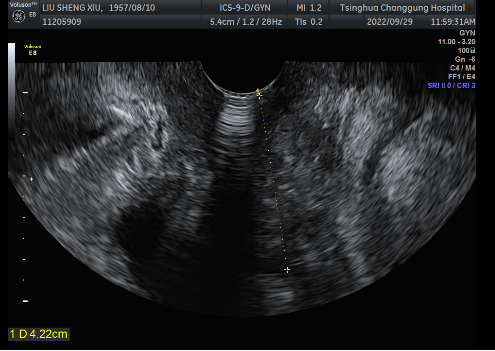

盆腔核磁可见直肠下段前壁增厚,可见不规则肿块形成,位于腹膜反折以下,肠壁较厚处约23mm,阴道后壁受压

阴道后壁与直肠前壁间可见不均质实性肿物,范围约3.8cmx2.9cmx2.3cm,可见较丰富血流信号,近端距阴道口约0.54cm,远端距阴道口约4.22cm